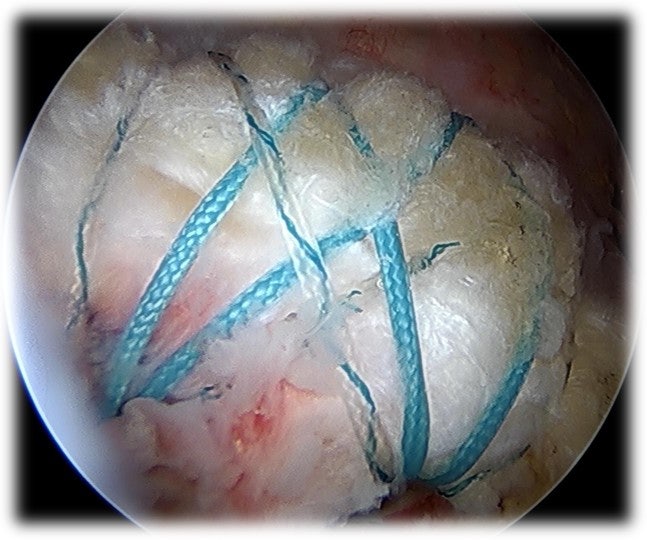

안녕하세요. 정형외과 전문의 이동규 입니다. 오늘은 회전근개 파열에서 관절경 수술시 더 단단하게 봉합하는 이열 봉합법을 시행한 케이스를 소개해 드리겠습니다. 회전근개 파열이 많이 진행 되었을때 단순히 봉합만 해서는 회전근개의 장력을 견디지 못해 재파열이 일어날 수 있습니다. 또한 파열이 된지 오래 되었다면 힘줄의 퇴행성 변화가 많이 진행되어 재파열이 일어날 수도 있습니다. 이열 봉합법은 이중으로 회전근개를 봉합하는 술기 입니다. 즉, 회전근개가 상완골에 부착되는 부위를 foot print 라 하는데 이 부위를 이차원적이 아닌 3차원적으로 면으로 봉합하는 방법이라고 생각하시면 됩니다. 보여드릴 케이스는 67세 여자환자 분입니다. 오랜 기간동안 통증이 있어 왔고 주사치료만 받았던 분이었습니다. 최근에는 주사치료에도 통증이 좋아지지 않고 일상생활도 불편해지고 밤에 잠을 자지 못할 정도로 통증이 있어 본원으로 내원하게 된 환자분입니다. 이학적 검사상 impingement sign, empty can test 양성 소견을 보였습니다.

중파열 정도로 보이며 관절경을 통한 회전근개 봉합술을 시행하였습니다.